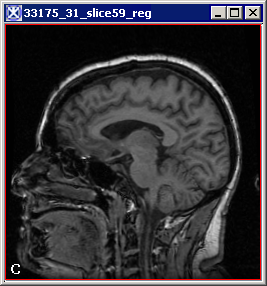

The input source image (A), the input target image (B) and the output registered image (C). Note that images (A) and (B) are both the images of the same brain. That's why it shows a very good overall fitting. Results may vary, if you take different brain images.